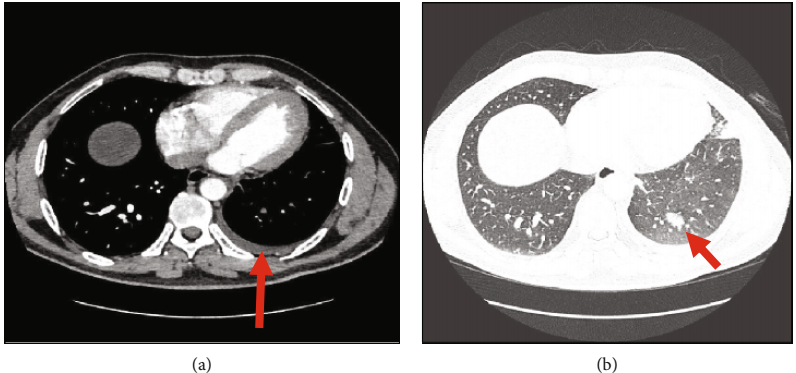

然而,两个月后,患者出现咳嗽并伴有咯血和轻微的左侧胸痛。他接受了计算机断层扫描肺血管造影(CTPA),显示左上叶和舌部有多个实变斑块和磨玻璃样混浊,并伴有少量左侧胸腔积液(图1a,b),推测可能是感染或肺梗塞。患者被给予广谱抗生素治疗,并转诊至呼吸科作进一步调查。同时,在心脏病门诊接受随访,由于在活动性咯血的情况下,患者的CHA2DS2-VASc评分为零,因此建议停止服用利伐沙班。

图1. 计算机断层扫描:(a)左侧胸腔积液(箭头);(b)左心室实变和GGO(箭头)。GGO:磨玻璃样混浊;LUL:左上叶